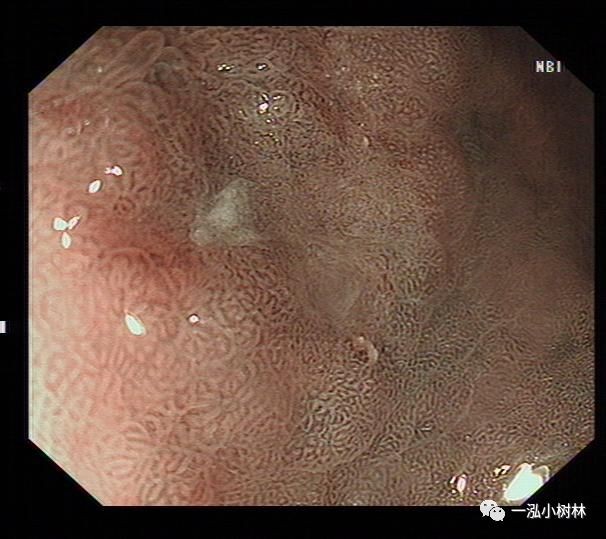

NBI+ME内镜表现:萎缩区域NBI放大可见胃小凹消失或不清晰,树枝状血管显露,黏膜苍白及萎缩边界更明显,多以幽门胃窦部为中心,随着萎缩的加重,胃体黏膜也散见,肠化区域可见胃小凹呈绒毛状,可见到“亮蓝嵴”“白色不透明物质”征。

例3

女性,40岁,萎缩性胃炎+Hp感染